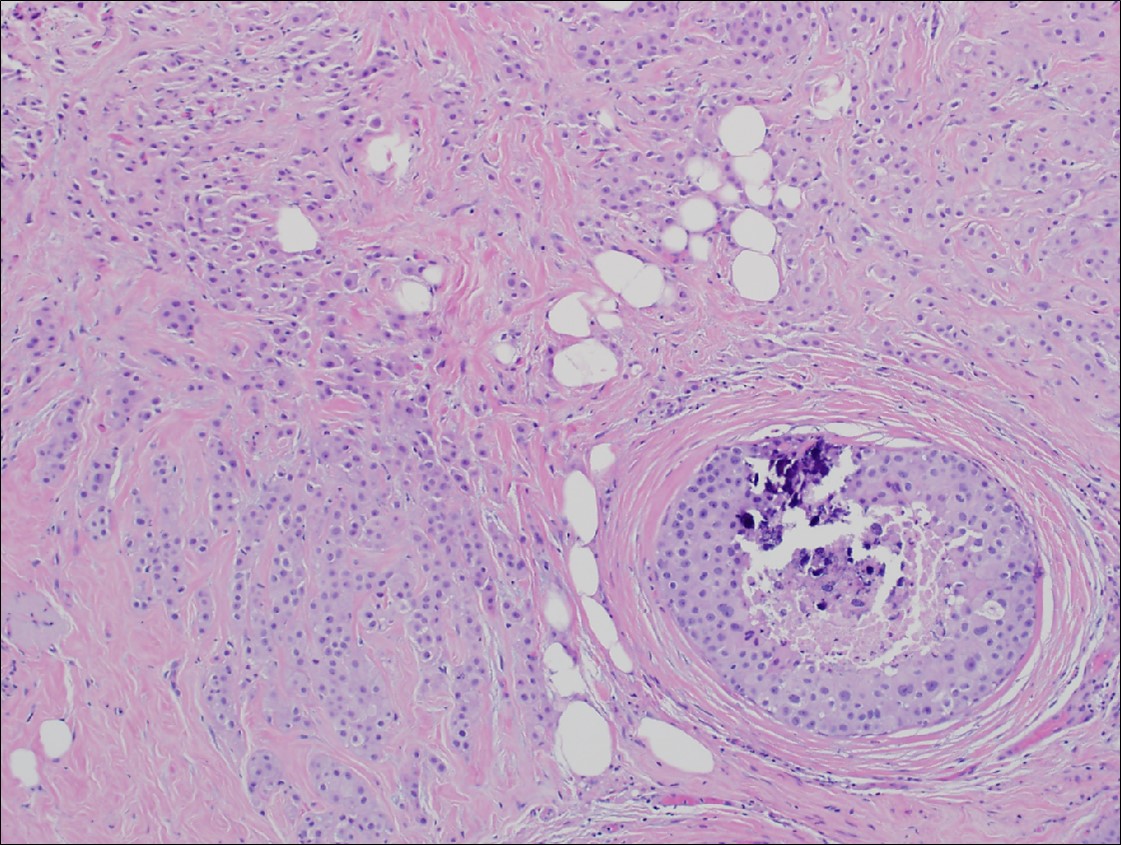

Microscopic (histologic) description

- Histological features of IBC NST vary considerably from case to case and even within the same case

- Margins vary from highly infiltrative, permeating the surrounding tissue, to continuous pushing margins

- Architecture varies from sheets, nests, clusters, cords or individual cells (but lacks the cytomorphological characteristics of invasive lobular carcinoma)

- 2 distinct growth patterns exist:

- Tumors characterized by small cancer nests accompanied by marked fibrosis (desmoplastic / scirrhous); this type diffusely infiltrates the surrounding tissue as an irregular shaped spiculated mass

- Calcification in 60% of cases, variable necrosis

- Elastosis involves stroma, wall of vessels and ducts and causes grossly noted chalky streaks

- Often ductal carcinoma in situ (DCIS) (up to 80%)

- Perineural invasion (28%)

- Angiolymphatic invasion in 35%; differs from tissue retraction because:

Microscopic (histologic) images

Contributed by Julie M. Jorns, M.D., Kristen E. Muller, D.O., Gary Tozbikian, M.D. and Emad Rakha, M.D.